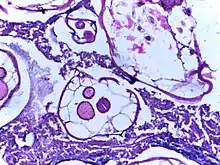

![]() | Rhinosporidiosis | Section of a polyp containing Rhinosporidium seeberi | Category: Histopathology of rhinosporidiosis | Rhinosporidiosis |